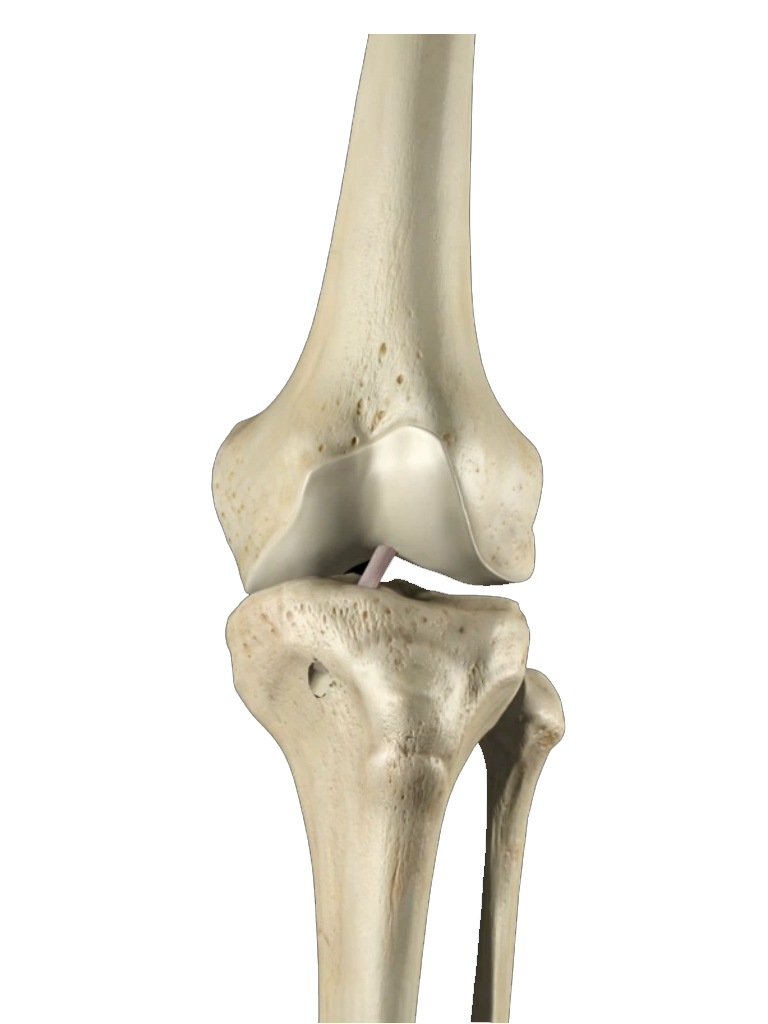

La artroscopia de rodilla es un procedimiento de mínima invasión en el que se hacen dos pequeñas incisiones de 4 mm a cada lado de la rodilla. Este método nos permite reparar lesiones de meniscos, que es la patología más común en larodilla; lesiones ligamentarias, lesiones del cartílago articular. Es útil también como método auxiliar en algunos procedimientos combinados en donde se utiliza cirugía convencional para fracturas y con control artroscópico se cuida que la articulación quede en óptimas condiciones.

Actualmente la lesión de Ligamento Cruzado Anterior (LCA) ya no implica un problema su reparación y aún en deportistas de alto rendimiento pueden retornar a su alto nivel deportivo. La cirugía sin embargo, requiere de alta precisión para su éxito, por lo que requiere de una alta experiencia por parte del cirujano ortopedista. El procedimiento se realiza por tres incisiones, dos de 4 mm y una de 1 a 2.5 cm, por una de las incisiones menores se introduce la cámara con la que se revisa toda la articulación, por otra de las pequeñas incisiones se introducen los instrumentos necesarios y por la tercera se obtiene y se tuneliza el nuevo ligamento.